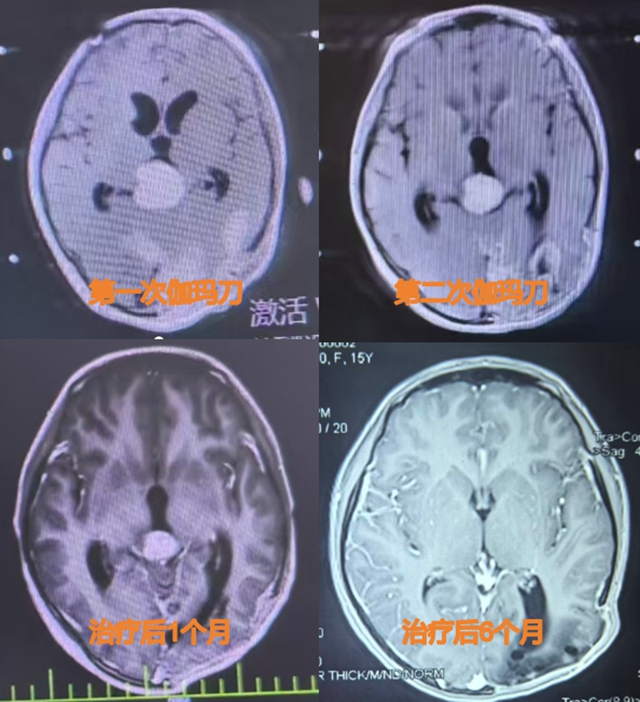

据龚飞龙介绍,伽马刀放射治疗具有单次剂量高、治疗周期短的优势,对于术后情况不稳定、无法承受普通放疗多次治疗的小汪来说,无疑是最可行的方案。为缩短单次治疗时间,保证小汪安全,医生决定分两次进行伽马刀放射治疗,中间仅间隔5天。

幸运的是,第一次伽马刀放射治疗后,小汪的脑肿瘤体积就缩小了50%。两次伽马刀放射治疗后,脑肿瘤体积更是缩小了80%。目前,治疗后7个月的小汪脑肿瘤已完全消失,眼球活动完全恢复正常,视力也恢复了正常。